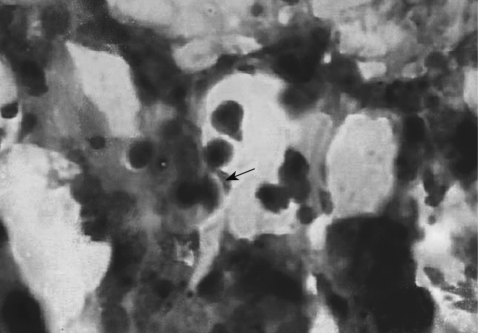

To examine the infection status of visceral organs after intraduodenal inoculation, the brain, heart, liver, lung, stomach, duodenum, jejunum, ileum, kidney, and spleen of mice were removed. These organs were fixed in 10% neutral formalin and embedded in paraffin. The embedded sections were cut into a thickness of 4 µm, stained with Giemsa, and examined for tachyzoites under a light microscope.

Histopathologic examinations